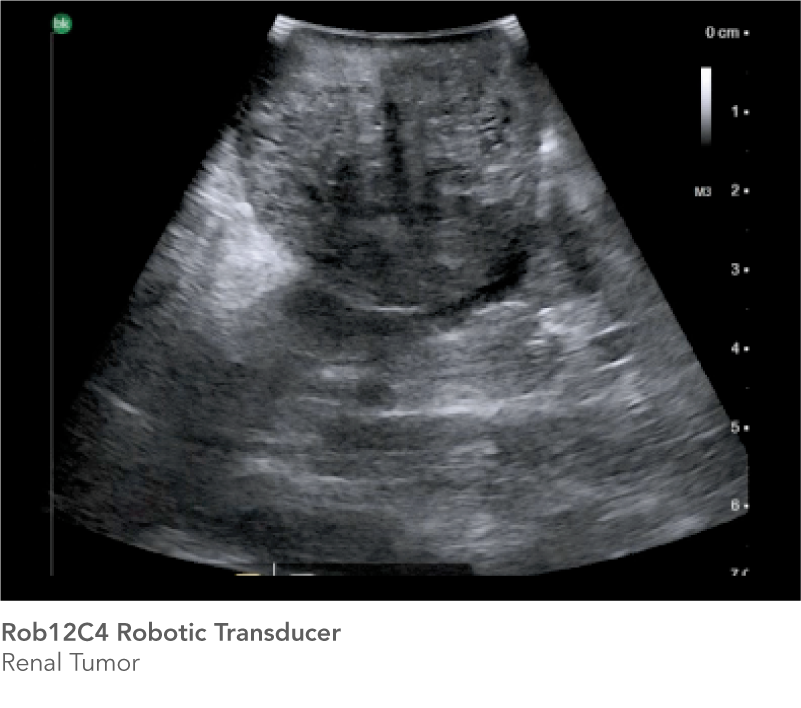

The Rob12C4 Robotic Transducer does more than Partial Nephrectomy. The high-resolution ultrasound transducer is designed to support robotics programs in a variety of procedures.

Partial Nephrectomy

See the information you need to achieve successful outcomes

Real-time intraoperative ultrasound helps you confirm tumor borders and depth, and minimize warm ischemia time, positive margins, damage to arteries, and resection of healthy tissue. The Rob12C4 transducer features a highly flexible cable and a small transducer profile, while the bk5000 offer's outstanding image quality with excellent anatomical details, enabling you to reach difficult-to-access anatomy and see the information you need to achieve successful outcomes.